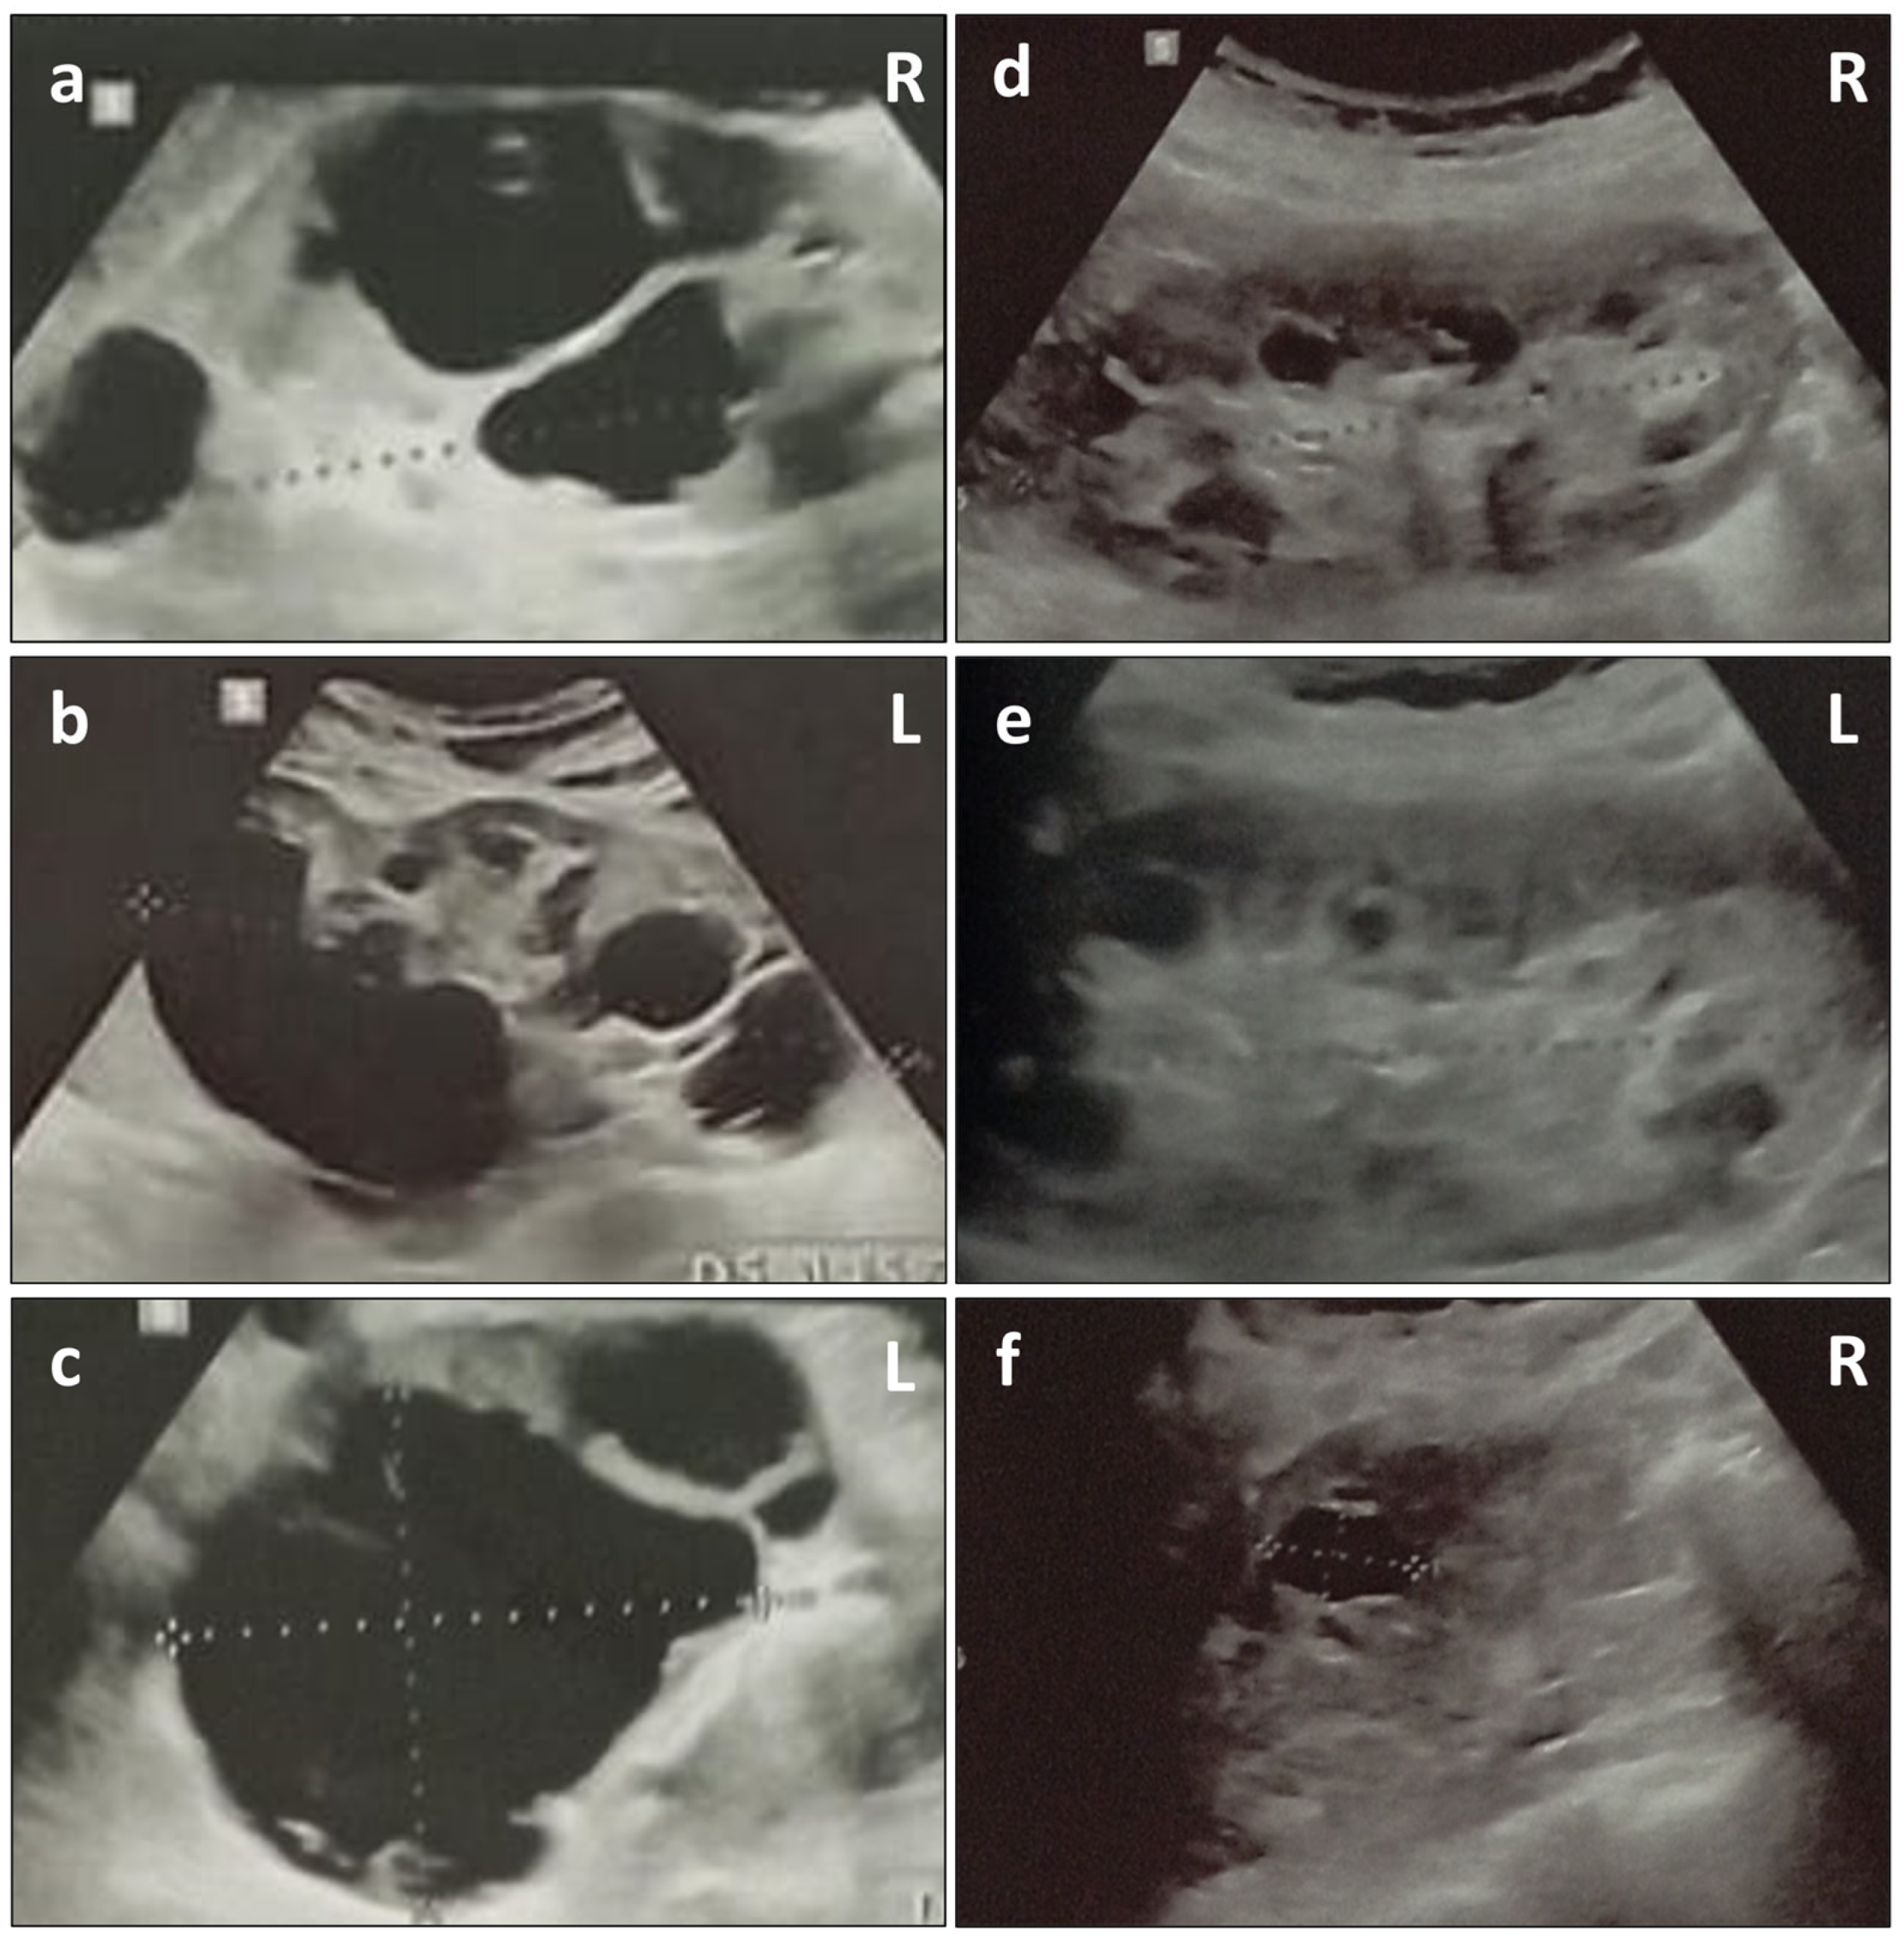

2. Case Presentation